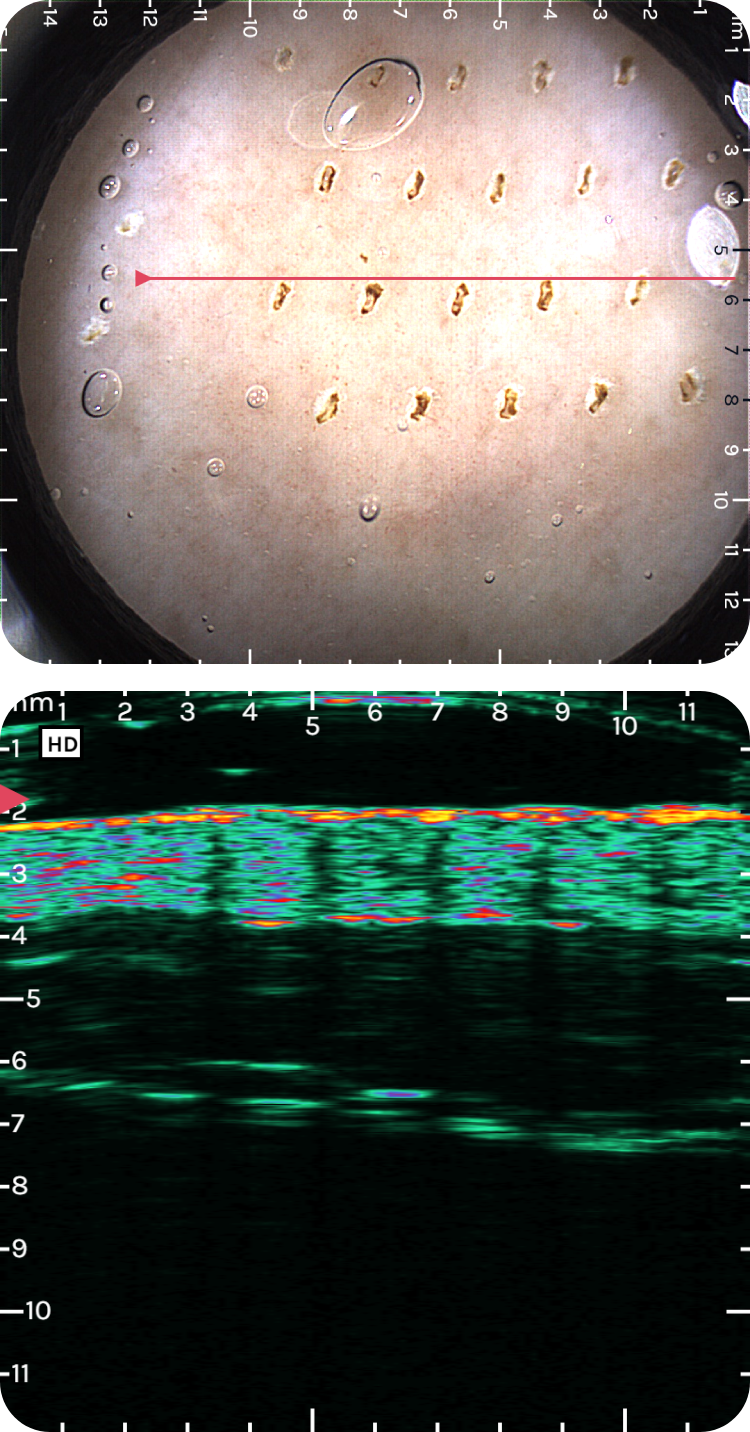

Dermoscopy guidance with 12x12 mm optical field of view

Highest frequency handheld ultrasound on the market (20-40 MHz, ≤10 mm depth)

Easy interpretation with positioning line

1-D Power Doppler mode